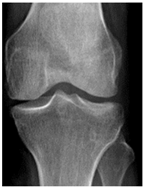

In the local dataset, we have selected 60 adult patient files of men and women with knee disorders who were radiographically examined at the Radiology Department of the El Kelaa des Sraghna Provincial Hospital. Each file consists of one or more knee radiographs in Dicom format as presented in Figure 7. The images were acquired using a standard ITALRAY radiology table. After analysis, 30 images with implants and non-posterior-anterior examination views were excluded and 30 left and right Dicom knees were retained to validate this work. To make the validation local dataset, the ROI was selected manually as illustrated in Figure 8. Then, each patient’s file was presented to a rheumatologist with PNG images. In case of disagreement between our diagnostic system and the rheumatologist, a radiologist was consulted for arbitration to make the final decision.

Figure 7.

Example of knee X-ray images collected and filtered from patients with knee symptoms.